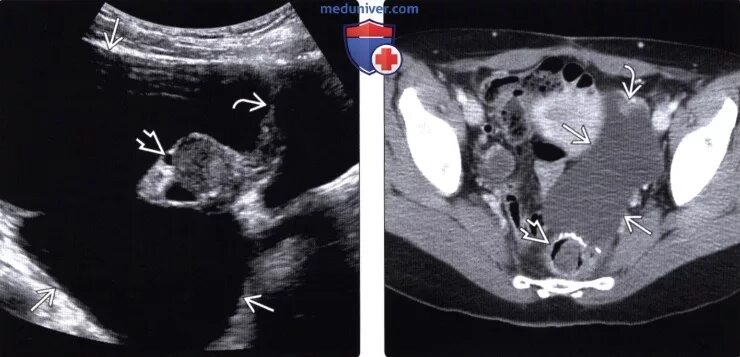

Солидное образование в малом тазу